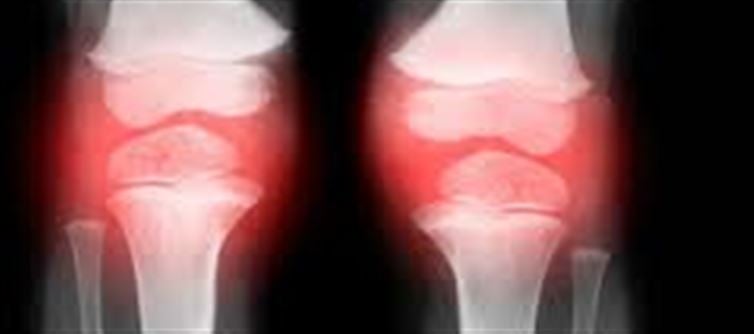

Strong bones are essential for body structure, mobility, and overall health. They not only support physical activity but also help maintain calcium balance, which is vital for muscle function, energy, and dental health. According to Dr. Akhilesh Yadav, understanding the causes of weak bones and taking preventive measures early can significantly improve long-term bone health.

Weak bones, or low bone density, can develop due to several factors: